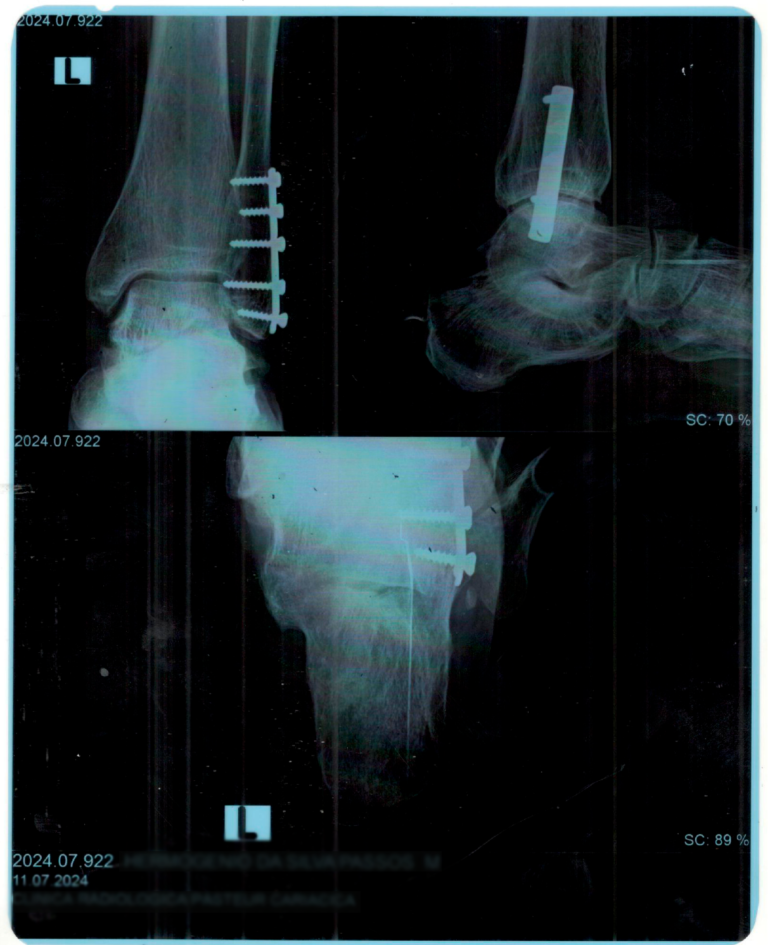

Uma professora lesionou o tornozelo em uma queda, ficando com dificuldade para ficar em pé por longos períodos. A sequela permanente garantiu o auxílio acidente.